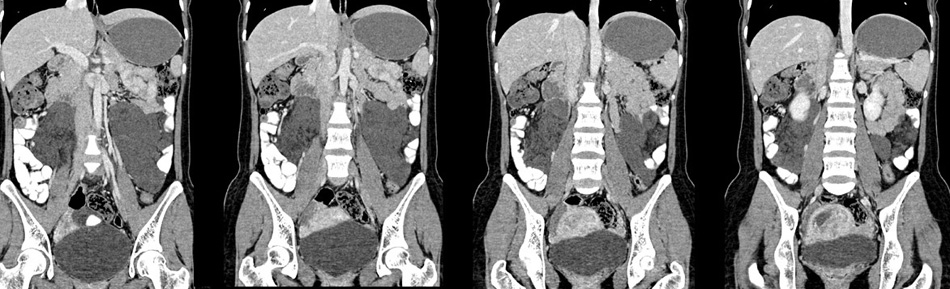

女性,28岁,停经3月,腹部膨隆1月,产前检查发现腹部占位

{肿块中心ct值27hu,增强后,动脉期、门脉期均无明显强化)

1 肠系膜肿块诸期无明显强化,肠系膜血管包绕其中但其周围仍见脂肪称“脂肪环征”;2 肠系膜血管远端较近端细,于重组像上见血管周围有强化结节为炎性结节,3肿块内见部分脂肪密度及少许点状钙化。4 腹膜后无肿大ln。

需与恶性病变鉴别,脂肪环征为重要点。亦需与卵巢源性肿瘤鉴别,年龄以及未见“卵巢静脉征”为要点。

患者手术病理:腹腔囊性淋巴管瘤,象这样充满整个腹腔的的确很少见